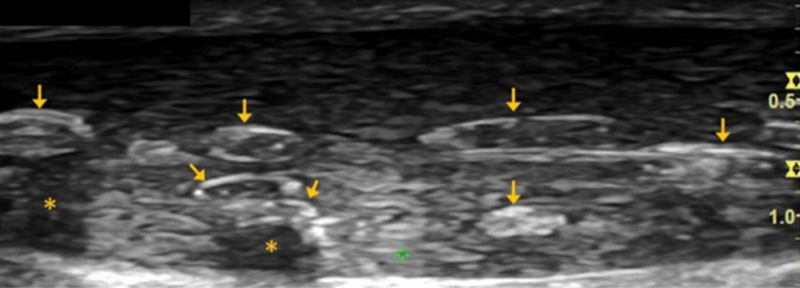

跟腱焦磷酸钙沉积病